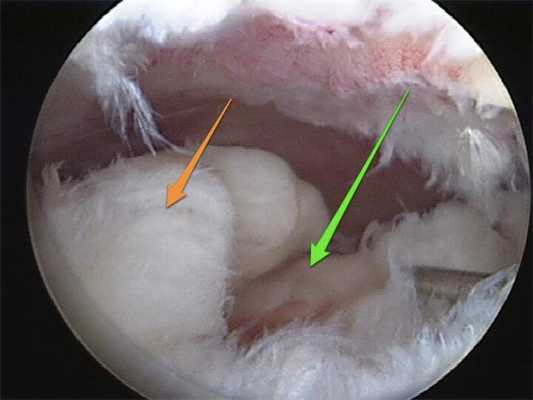

• Патологическая синовиальная складка (рис. 1)

РИСУНОК 1. Медиопателлярная синовиальная складка в переднем отделе коленного сустава до (А) и после (Б) резекции. РИСУНОК 2. Синовиальный хондроматоз. Предоперационные рентгенограммы в прямой (А) и боковой (Б) проекциях. (В) Артроскопическая картина износа суставного хряща вследствие образования в полости сустава множественных свободных хондромных тел (Г). РИСУНОК 3. Воспалительная кристаллическая артропатия с отложением кристаллов солей в ткани мениска (А), образованием свободных депозитов (Б) и клинически значимой хондромаляцией (В). РИСУНОК 4. Картина септического артрита: инфицированная синовиальная жидкость (А), (Б) сформировавшая вокруг аллотрансплантата передней крестообразной связки биопленка до ее дебридмента (В).